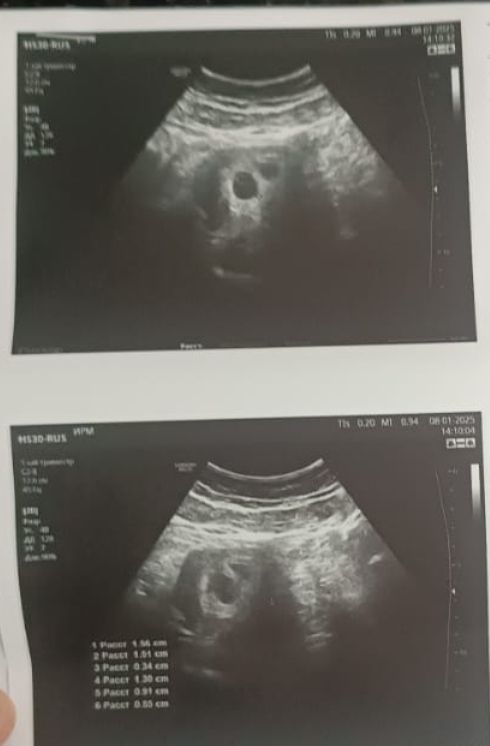

Это УЗИ ре сделала 5+5 дней

Здравствуйте девочки помогите пожалуйста 7 недель +6 дней беременности эко. Вчера было на УЗИ сказали что гематома, у плода ♥️ есть услышали, когда мне сделала УЗИ 5 недели 5 дней два плодное яйцо было вчера врач ничего не сказала просто сказала что есть гематома леди дома ато будет выкидыш я и так дома лежу ничего не делаю только отдыхаю.